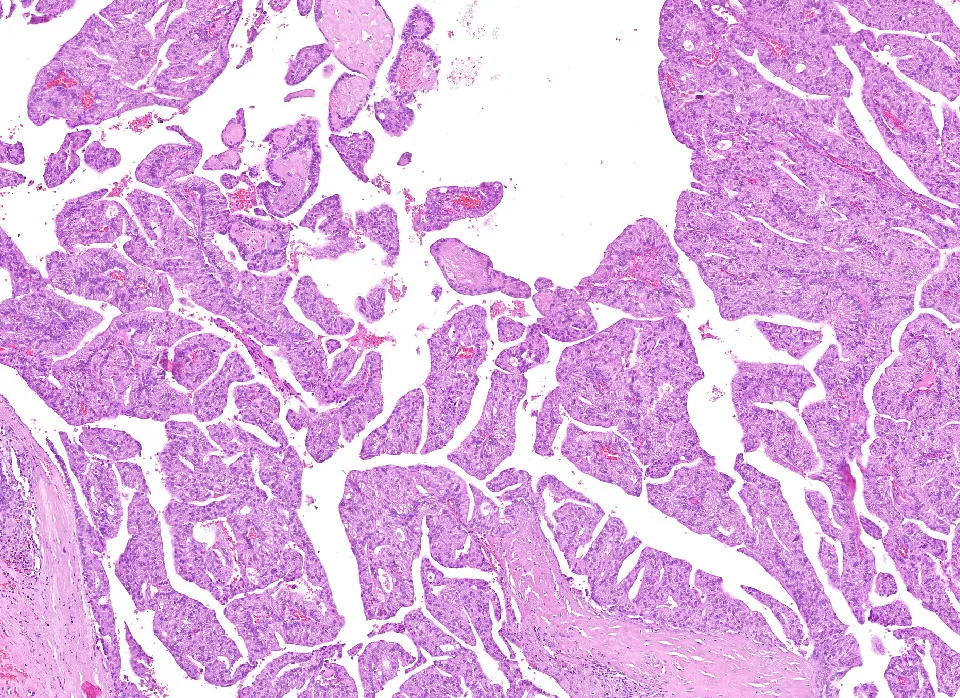

3-H&E3

Diagnóstico: Adenocarcinoma mucinoso, anteriormente denominado cistoadenocarcinoma papilar, de grado intermedio de localización amigdalar.

- Histológicamente se caracterizan por áreas quísticas y sólidas con múltiples proyecciones papilares luminales que tienen un núcleo fibrovascular y están revestidas por células epiteliales cúbicas, columnares o secretoras de moco. Inmunohistoquímicamente es CK7, CEA y EMA positivo, siendo negativo para otros marcadores de glándula salival. (PMID: 35252049)

- Algunos autores hablan de un sistema de clasificación dual, en neoplasias de bajo o alto grado, estas últimas suelen tener características localmente agresivas con invasión estromal, atipia citológica, tasa mitótica alta, necrosis y ausencia de características papilares. Aunque nosotros hemos gradado la neoplasia acorde a los parámetros de gradación de la OMS (grado intermedio). (PMID: 30918612)